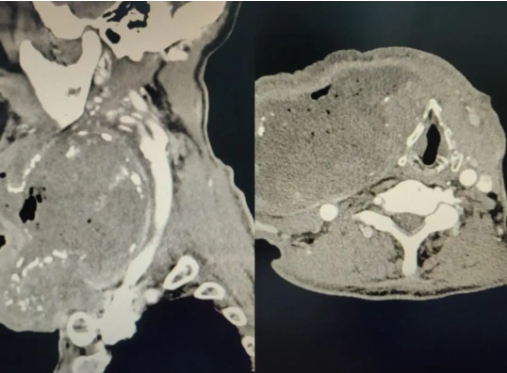

接诊时,经完善颈部CT等相关检查,发现覃爷爷颈部肿物来源于甲状腺肿瘤,血管供枝血流丰富,右颈部的静脉受压至严重变形,压迫气管并向左侧推移,同时肿物持续流脓,出现严重感染并伴有高热、重度贫血、低蛋白血症等症状,如果继续搁置,不及时进行处理,有可能会出现感染性休克甚至危及生命,遂覃爷爷住院进行下一步治疗。

术中,为了实现患者术后快速康复,手术团队取患者颈前区皮纹处做低领弧形切口,在切开肿瘤之后,发现肿物底部与颈部动静脉紧密粘连,喉返神经走形刁钻,气管及食管均受压迫移位,局部解剖关系复杂,无疑增加了手术的难度和风险。但手术团队凭借丰富的临床经验和精湛的手术技巧,在充分保护区域血管、神经完整性的情况下,一点点对粘连组织进行剥离,最后,顺利完整切除患者颈部罕见巨大肿瘤,出血量仅为20ml,术后患者恢复良好,复查时各项指标均正常。